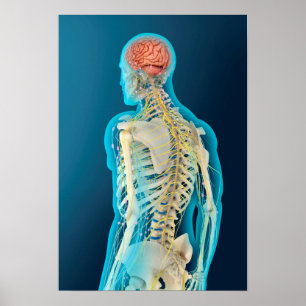

Poster da anatomia do cérebro humano

Preço47,55 €